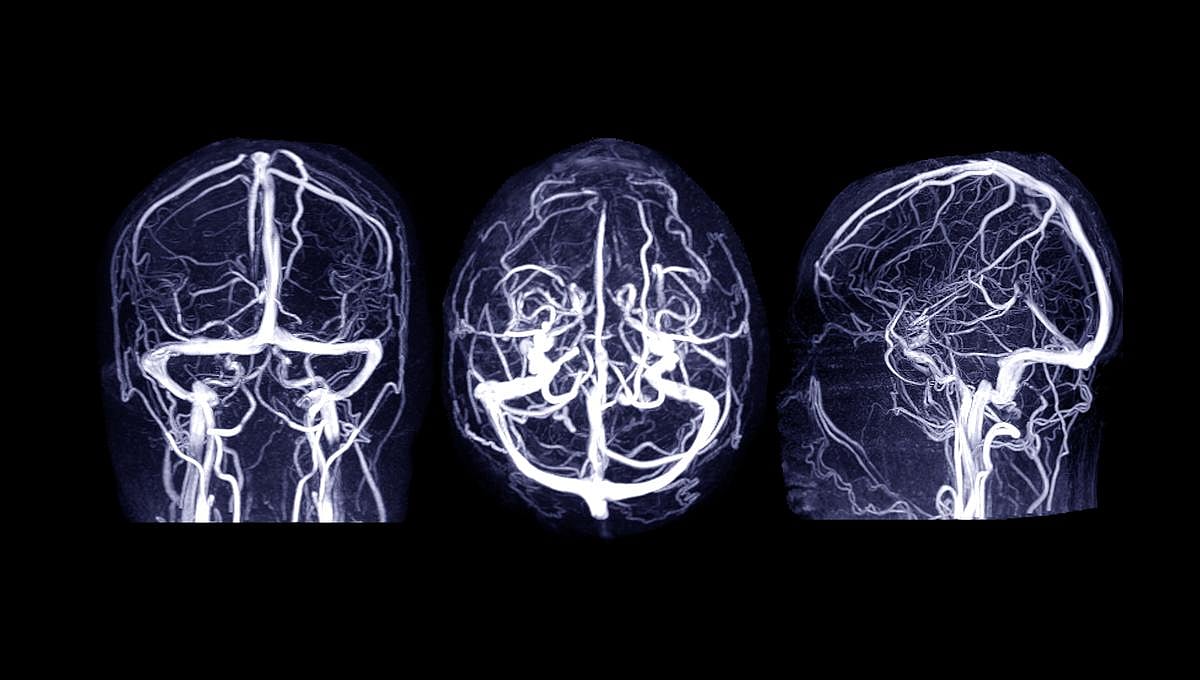

Young adults who develop eating disorders appear to have delayed brain maturation as teenagers, MRI scans show in a new study published Jan. 10 in the journal Nature Mental Health.

For the study, researchers analyzed data from nearly 1,000 people in England, Ireland, France and Germany. The participants all underwent MRI scans at ages 14 and 23, provided samples for genetic analysis, and completed questionnaires related to their eating habits.

The MRI scans revealed that these mental health problems and subsequent eating disorders might be explained by slower maturation of some participants’ brains.